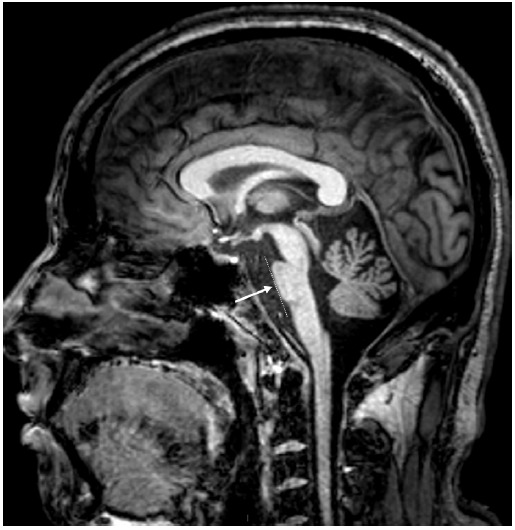

图12 患者头颅MRI 影像。头颅MRI T1加权序列显示脊髓小脑性共济失调2型(SCA2)相关的小脑萎缩。脑桥稍扁平(箭头,左侧)和小脑扁桃体保留(箭头,右侧)。

图13 患者头颅MRI 影像。头颅MRI T1加权序列矢状位图像显示脊髓小脑性共济失调2型相关的小脑和脑干萎缩。脑萎缩和脑桥扁平(箭头);可能的脊髓变细。